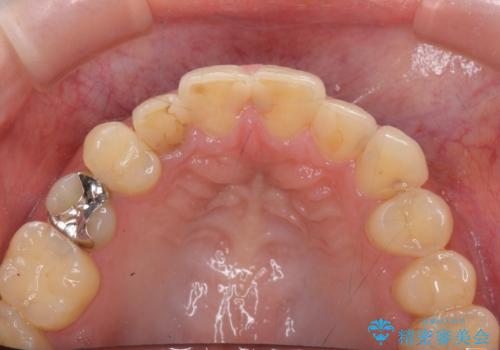

- 神経をとった前歯の変色や、前歯の充填物の変色が大きくなってきたので審美性の改善を求めて来院されました。

充填物や充填物下に再発した虫歯を丁寧に除去し、セラミッククラウンによる審美性の改善、虫歯治療を計画します。

レジン修復による充填は、劣化し、色調の変化による審美障害が生じることが多々あります。

ある程度の大きさになった充填物は、劣化の少ないセラミッククラウンにすることで色調の劣化を抑え、審美性を保つことができます。